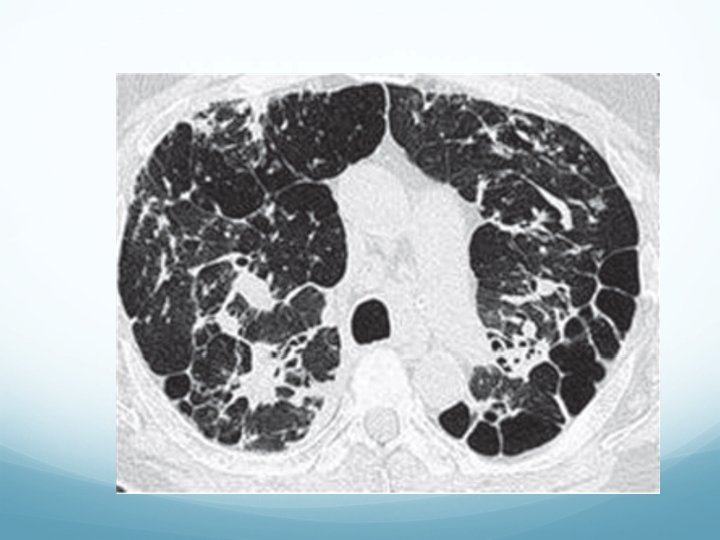

5 -Patología pulmonar intersticial. Enfermedades pulmonares intersticiales difusas EPID �Las enfermedades pulmonares intersticiales difusas EPID son un grupo de enfermedades con manifestaciones clínicas, radiológicas y funcionales respiratorias similares y con afectación de las estructuras alveolointersticiales

EPID Clasificación � Neumonías intersticiales idiopáticas. � Fibrosis pulmonar idiopática. � Neumonía organizada criptogenética. � Neumonía intersticial aguda. � EPID de causa conocida. � Enfermedades del colágeno ( AR, dermatomiositis, lupus, Sjogren, � � esclerosis sistémica, etc). Fármacos ( Amiodarona). Radioterapia. Neumoconiosis. Alveolitis alérgicas extrínsecas. � EPID primarias o asociadas a procesos no bien definidos. � Sarcoidosis

Enfermedades pulmonares intersticiales difusas-EPID Pruebas funcionales �Disminución de la FVC. �Disminución de la TLC. �Disminución de la difusión. �Hipoxemia sin hipercapnia. �Desaturación al esfuerzo en TM 6 M.

FIBROSIS PULMONAR IDIOPATICA �Es una EPID del grupo de etiología desconocida. �Afecta a personas de >50 años. �Poco frecuente, pero aun así es la más frecuente de las EPID. � 15 -20 casos por 100. 000 habitantes. Unas 7. 000 personas en España Fibrosis asociada a AR 1 caso/100. 000 hab Fibrosis asociada a fármacos se estima menos 1/100. 000

Cuadro clínico �Inicio insidioso �Clínica de disnea progresiva y tos seca �No tiene síntomas extra-respiratorios �Crepitantes en la auscultación ( 90%) y acropaquias (20 -50%) �Sin alteraciones de laboratorio específicas �FVC, TLC y difusión disminuidas.